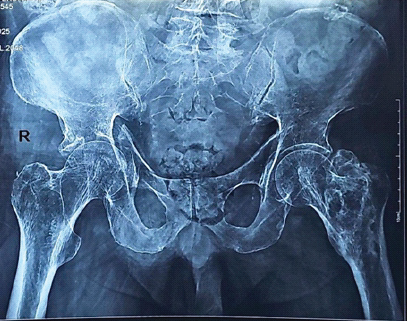

Management of Geriatric Acetabulum Fracture – A Case Report